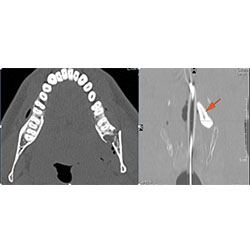

Mandible and Temporomandibular Joints

There is bony injury or displacement of the any part of the of the mandible including the condylar head and fossa.

Dentition